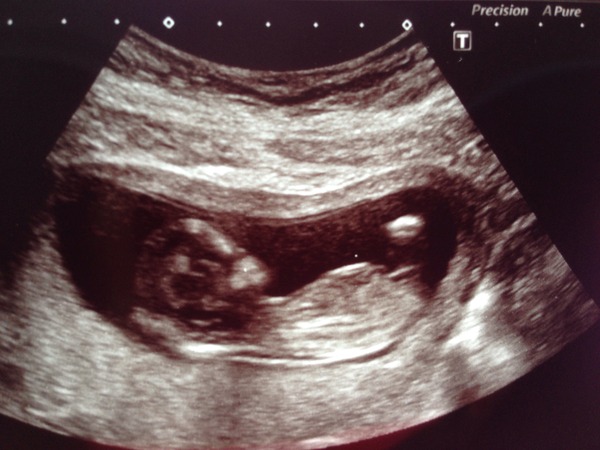

Oh and whilst we're sharing scan pics here's mine from yesterday. Definitely moved on from 8 week blob!

Jan 2016 #4 - heading for the end of the 1st trimester with dating scans and wacky dreams